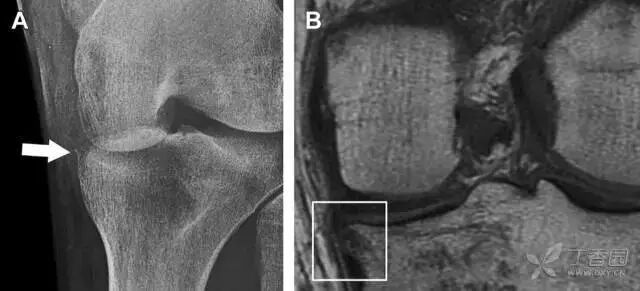

反向 Segond 骨折

胫骨平台内侧皮质骨撕脱性骨折,被称为内侧 Segond 骨折或反向 Segond 骨折(图 5)。这种骨折的旋转机制与 Segond 骨折相反,该骨折与后交叉韧带断裂及内侧半月板损伤相关。

图 5 一位足球运动员的反向 Segond 骨折。A 正位片示关节线处的胫骨内侧见一细小骨折片(箭头)。B MRI 冠状位 T1 加权像示骨折片出现在内侧副韧带关节囊附着处(方框)